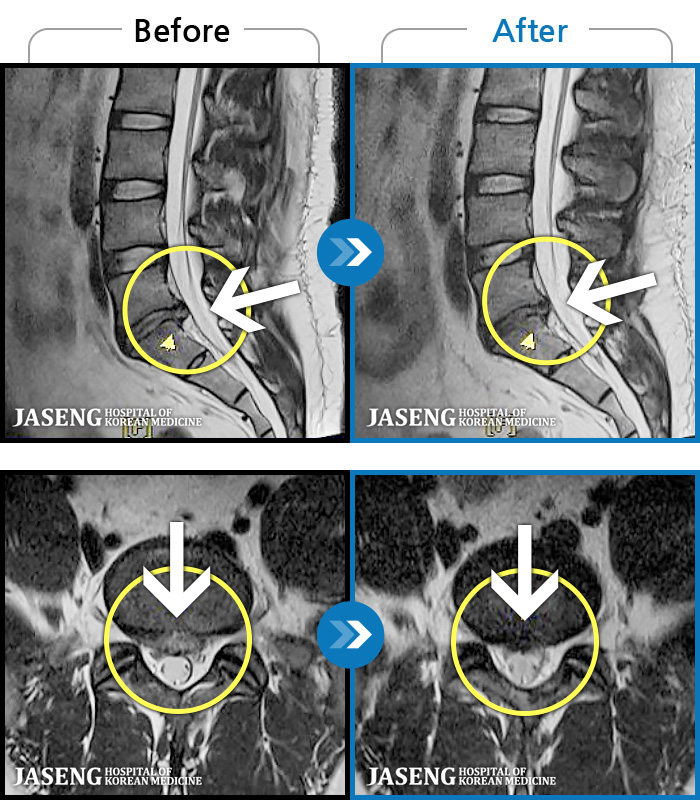

[] 03.04.01~09.11.01